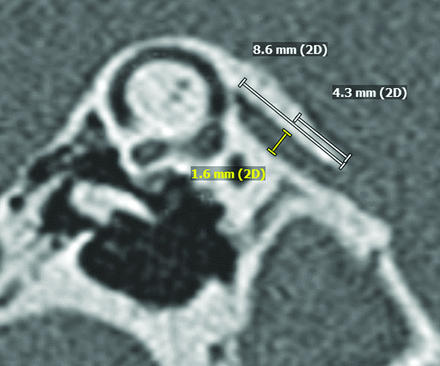

The Pöschl plane images (example in Fig 1) were independently reviewed by 2 blinded radiologists who determined the midpoint VA size using the technique outlined in Juliano et al.15 The mean midpoint VA size was determined and compared with the audiologic findings.

Measurement of the midpoint vestibular aqueduct size in the Pöschl plane. The length of the VA is determined, and the midpoint level is located. A measurement line perpendicular to the VA length is used to measure the midpoint VA size.